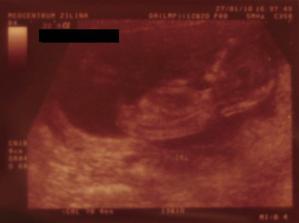

Onedlho nás uvidíte ako malé bodky na sone,